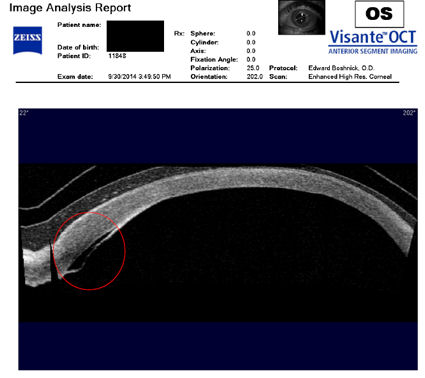

На рисунке ниже представлен снимок глаза пациента, перенесшего операцию по удалению RK в 1980-х годах, за которой последовала операция LASIK в 2003 году. В 2014 году пациентка внезапно потеряла зрение на левом глазу из-за эктазии роговицы. Внутриглазное давление, оказываемое на истонченную, ослабленную стенку роговицы, привело к разрыву внутренней оболочки роговицы (десцеметовой мембраны). На этом изображении, сделанном с помощью оптической когерентной томографии (ОКТ), вы можете видеть разрыв мембраны, обведенный красным кружком. Когда произошел разрыв, жидкость из глаза попала в роговицу, в результате чего роговица затуманилась, а зрение в этом глазу стало очень нечетким. Это состояние известно как "водянка". Вы заметите, что над роговицей находится склеральная линза, представленная двумя тонкими полупараллельными линзами. Назначение склеральной линзы - обеспечить зрение и защитить поврежденную ткань роговицы.